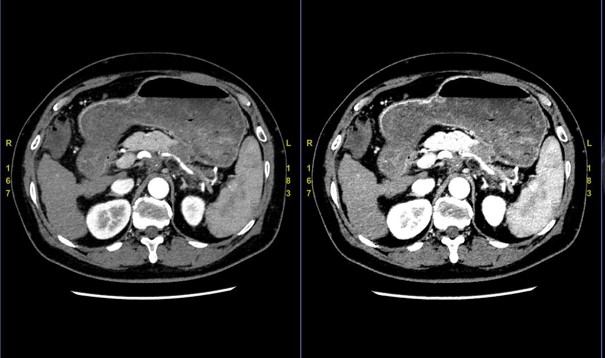

当院では肝胆膵におけるダイナミック検査は全例GSIによるDual Energy撮影を行っている。特に胆膵の腫瘍はコントラストに乏しいことがあるため、Monochromatic imageにおける低keV画像による読影は有用である。(図5)のように乏血性膵がんは低keV画像を用いることにより、腫瘍領域や脈管への浸潤が明瞭となる。

実際のGSI画像読影については読影医がAW Serverにて実施しており、当院ではGSIで撮影した際には全例1.25mmのGSIデータファイルをAW serverへ自動転送している。当院でのGSI画像読影では50keV画像とIodine mapを診る頻度が高く、AW ServerでのGSI画像専用の画像表示レイアウトを作成することで読影医がワンクリックでストレスなく読影できる環境を整えている。(図6)

RevolutionCT_Sasebo06.jpg

図6. 読影医のAWレイアウト(例)